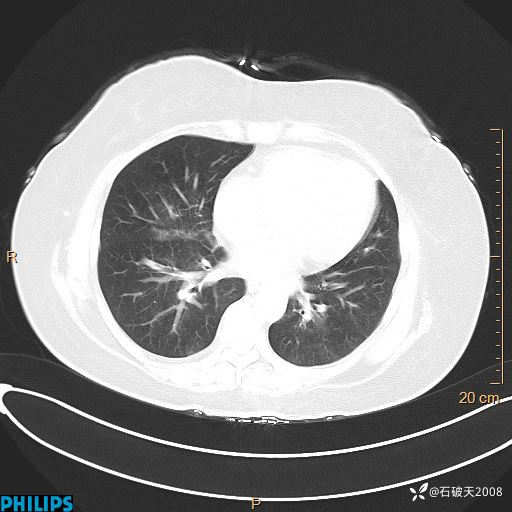

肺结节病?纵膈型肺癌?淋巴瘤?有点意思,欢迎围观

女 52岁 主 诉:咳嗽10余天,咳痰2天。

现病史:10余天前无明显诱因出现咳嗽,呈阵发性干咳,伴咽喉部发痒,无咽痛,无咳痰,无鼻塞、流涕、打喷嚏,无发热、畏寒、寒颤,无头痛、头晕,无胸闷、胸痛,无反酸、烧心,无腹痛、腹泻,无尿频、尿急,无皮疹等,在当地诊所求治,给予口服药物治疗(具体不详),病情无好转。遂在当地社区卫生服务中心开具口服药物治疗(具体不详),疗效欠佳。2天前出现咳痰,在我院门诊求治,行胸部CT提示肺部感染,建议住院,患者要求口服药物治疗,目前仍咳嗽、咳白色粘痰,白天量多,夜间自觉喉部喘鸣音,遂再次来院就诊,以“肺部感染”为诊断收入院。发病以来,神志清,精神可,饮食可,夜间睡眠差,大小便正常,近期体重无明显变化。

动脉期

静脉期